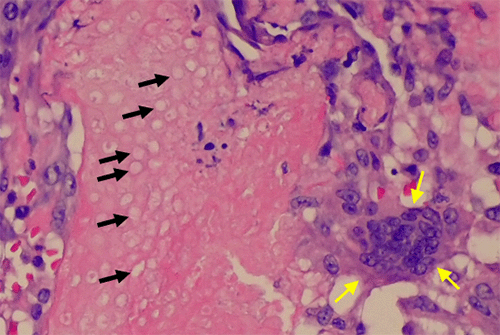

The patient tolerated the surgical procedure well without any perioperative complications. Pathologic examination revealed a formalin-fixed, 1.4 × 0.7 × 0.7 cm tan-red mass with a red-to-white, gritty cut surface. Histopathologic analysis demonstrated two distinct cell types: a basophilic cell type with mitotic figures and indistinct cell borders, and an eosinophilic cell type lacking nuclei and exhibiting more distinct borders. Additionally, multinucleated giant cells were noted within the surrounding tissue (Figure 3).

Figure 3. Histopathology of Excised Specimen (H&E Stain). Published with Permission

(C) This panel highlights a multinucleated histiocytic giant cell (yellow arrows) surrounding eosinophilic shadow/ghost cells (black arrows)

(D) High-power magnification reveals brisk mitotic figures (white arrows) within the basaloid cells

Histopathological hallmarks of PMC include islands of epithelial cells made up of basophilic cells, a transformation zone to eosinophilic shadow or “ghost” cells, and calcification.7,9,10,12 Additionally, studies have indicated that PMC tumors are often encapsulated in a thick layer of fibrous tissue.16,17 All of these histological markers except calcification were noted in our patient’s tumor (Figure 3).

The morphological progression of PMC is theorized to occur in stages. The first (“early”) stage is characterized by a small, cystic tumor. This progresses to the “fully developed” stage, with a larger, more cystic tumor and basophilic cells at the periphery. The “early regressive” stage is marked by islands of basophilic cells, shadow/ghost cells, and multinucleated giant cells. The final (“late regressive”) stage is characterized by a lack of basophilic and giant cells with calcification and ossification.18 Based on the histopathological findings, our patient’s PMC appears to have been in the “early regressive stage” at the time of diagnosis.